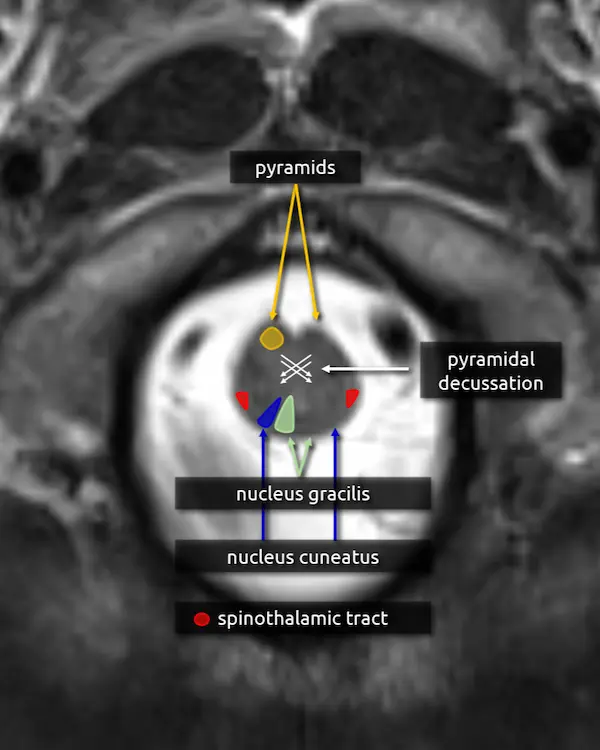

1. Pyramids:

The medullary pyramids contain the corticospinal tract and corticobulbar tract, which are sometimes collectively called the pyramidal tracts. They are named due to the shape they form on the ventral surface of the medulla, which usually becomes more pyramid-like inferiorly.

2. Pyramidal decussation:

The medulla transitions to the cervical spinal cord at about the level of the craniocervical junction. Right before this transition, about 90% of the corticospinal tract fibers traveling through the pyramids cross the pyramidal decussation before continuing through the spinal cord as the lateral corticospinal tract. The other 10% form the anterior corticospinal tract. On cross-sectional imaging, the approximate location of the decussation is inferred using the skull base and foramen magnum as landmarks.

8. Nucleus gracilis and cuneatus

Nucleus gracilis:

a. Located in the medial dorsal mid to lower medulla. It receives sensory input from the lower body (lower trunk, lower limbs) from T7 and below.

Nucleus cuneatus:

a. Located lateral to the nucleus gracilis. It receives sensory input from the upper body (upper trunk, neck, upper limbs) from T6 and above.

First order neurons carrying vibration, fine touch, and proprioception information from the spinal cord synapse with second order neurons in the nucleus gracilis and cuneatus. Second order neuron axons then decussate and travel superiorly through the medial lemniscus before reaching the third order neurons in the ventral posterolateral nucleus (VPL) of the thalamus. Collectively, this is called the dorsal column medial lemniscus (DCML) pathway.

1. Pyramids

2. Pyramidal decussation

3. Nucleus gracilis

4. Nucleus cuneatus